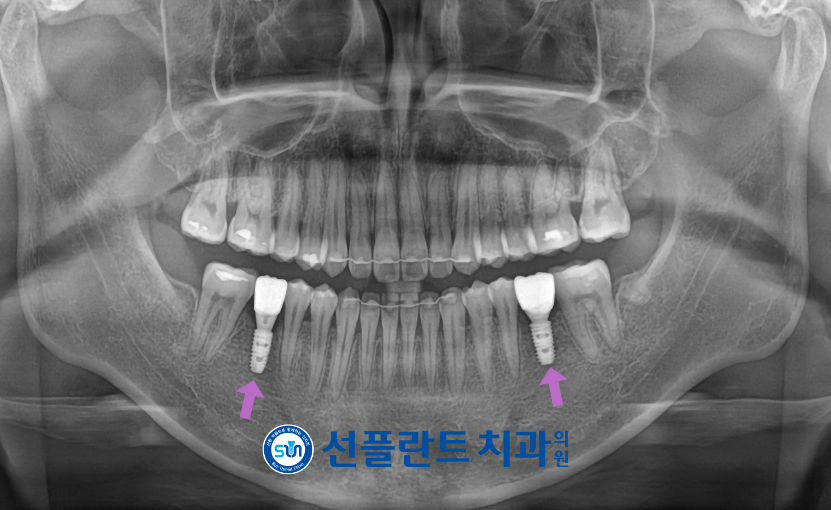

먼저 위아래 양측 사랑니 발치 후

아래턱에는 두 번째 큰 어금니(#37,47) 직립 유도,

위턱에는 악궁 확장을 진행하였으며

아래턱에 쓰러져 있던

두 번째 큰 어금니(#37,47)가

제 위치로 자리 잡고,

상실된 부위에

임플란트를 식립할 공간이 확보되었을 때

용인선플란트치과에서는

임플란트 식립을 도와드렸습니다.

식립 후 충분한 시간이 지났을 때

임플란트와 잇몸뼈가

단단히 결합된 것을 확인한 뒤

최종 보철물 제작을 위한

인상채득을 진행하였는데요.

최종 보철물은

자연치아와 강도가 유사하고

심미적인 지르코니아로

마무리해 드렸습니다.

모든 치료가 마무리된

구강 내 사진과 파노라마 사진인데요.